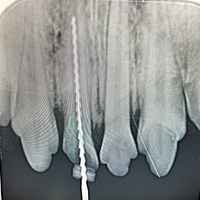

Eine umfassende und tiefgreifende Diagnostik ist auch in der Tiermedizin das A und O des Heilungserfolges. Nicht immer genügt eine allgemeine klinische Untersuchung, ein Tier zu begutachten, um eine eindeutige Diagnose zu stellen. Manche Symptome lassen kein eindeutiges Urteil zu, so dass wir in diesen Fällen auf bildgebende Verfahren wie Sonografie und digitales Röntgen zurückgreifen. So können Diagnosen schnell, konkret und direkt vor Ort in unserer Praxis erstellt werden.

- Digitales Röntgen